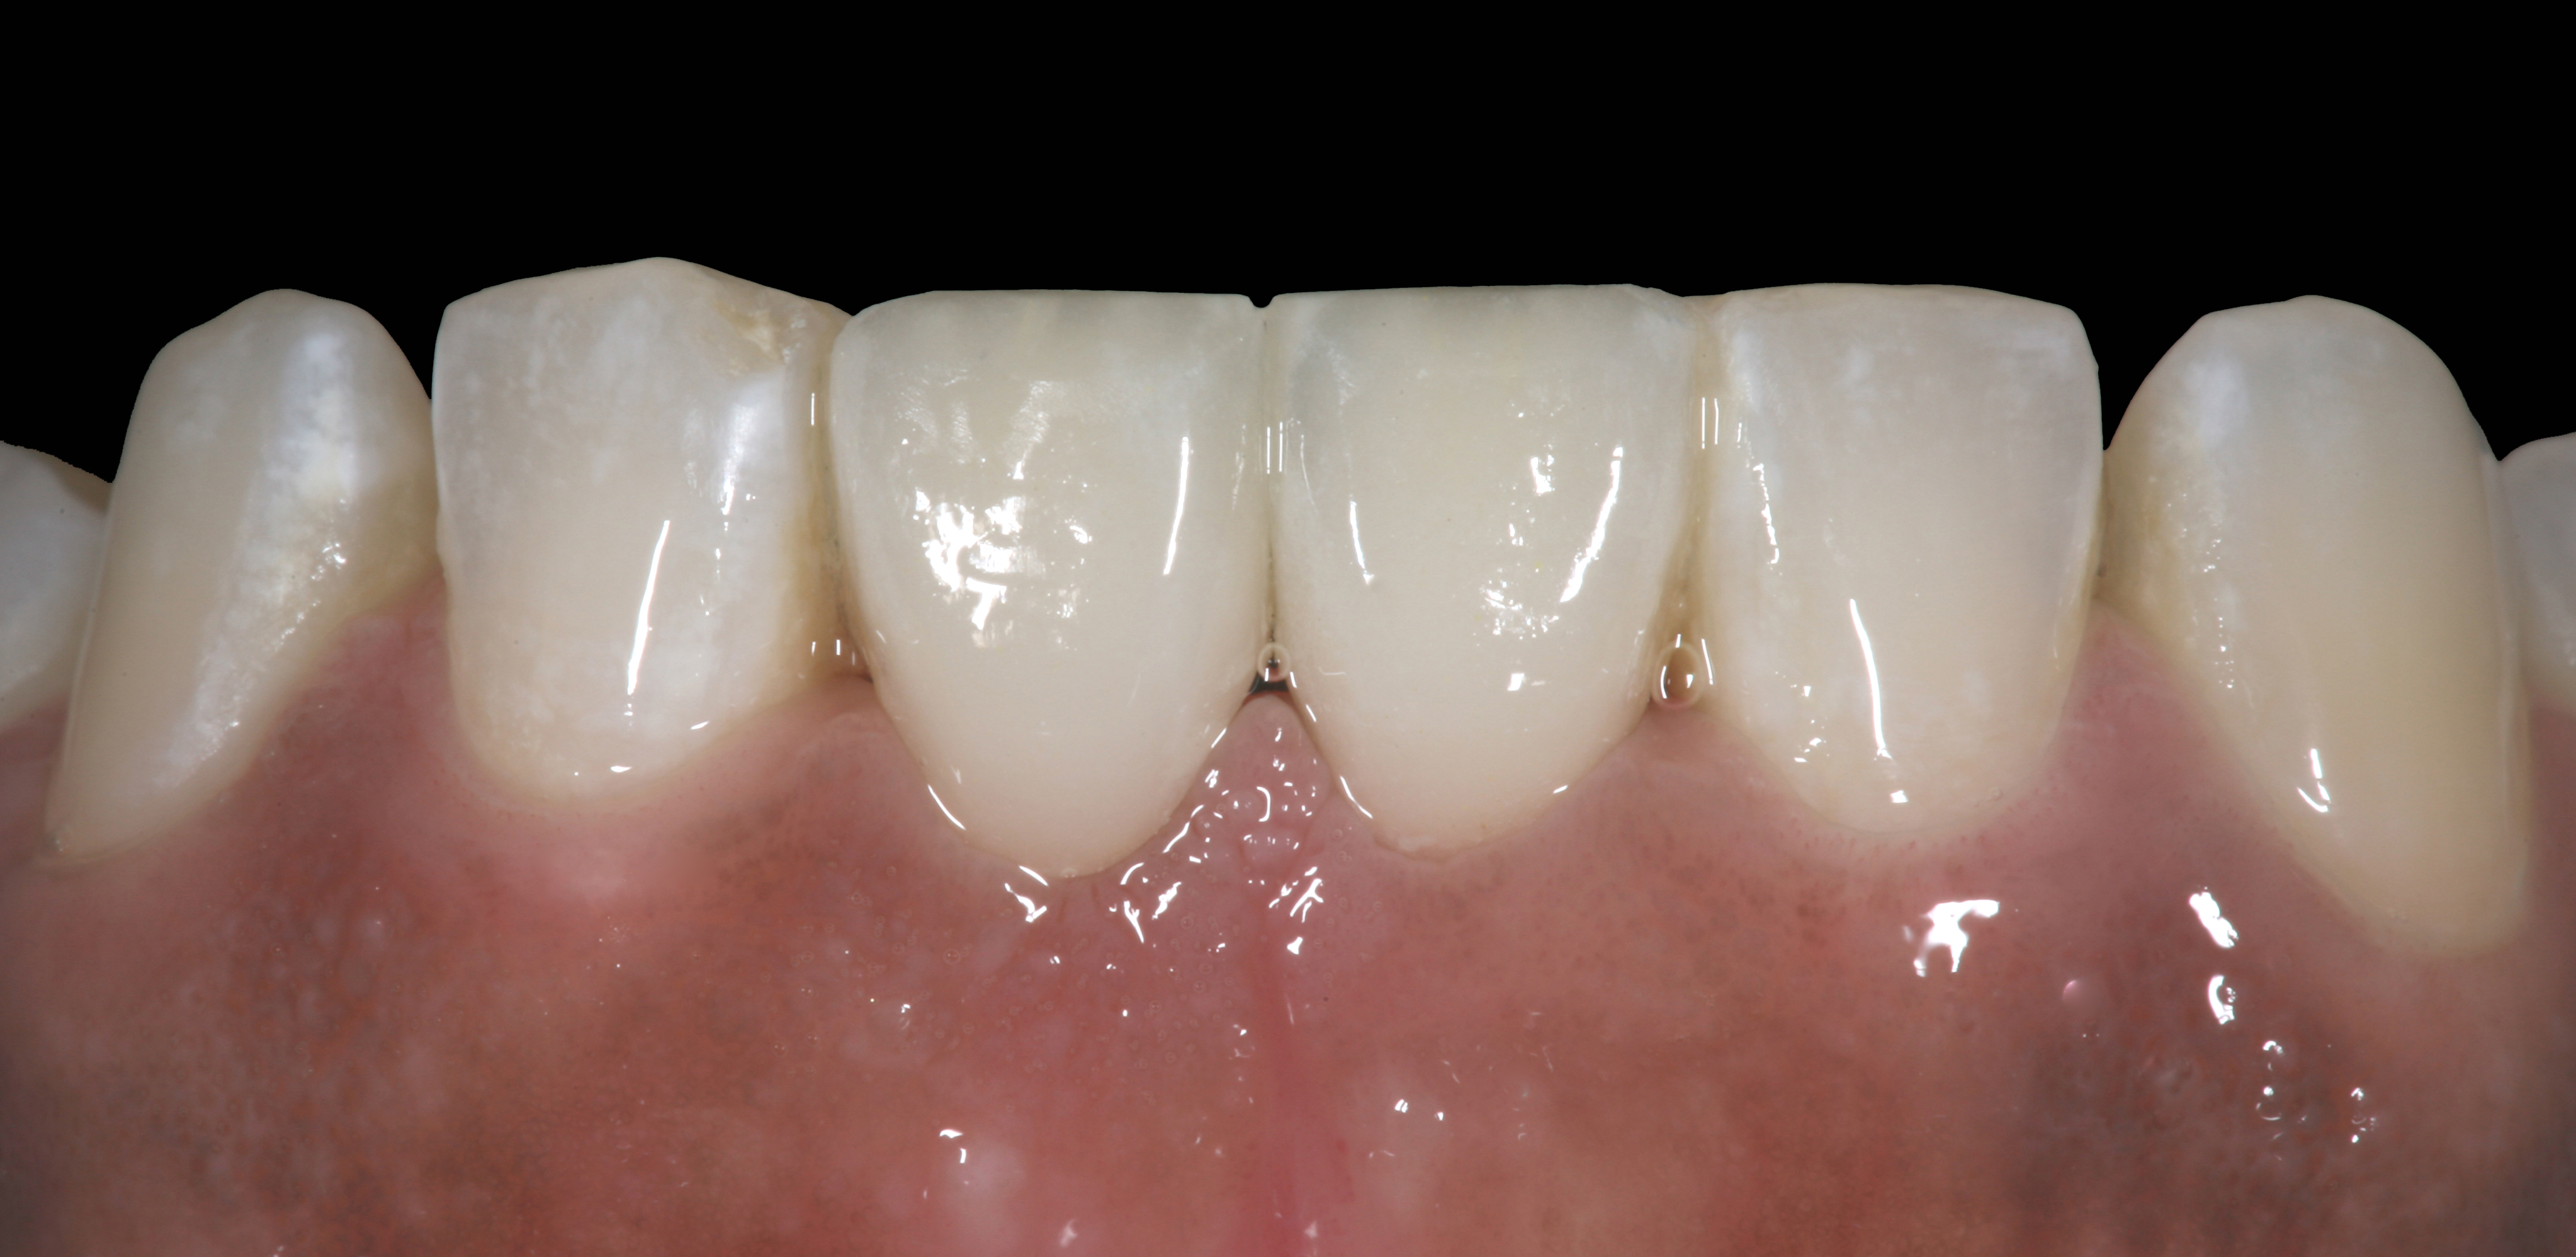

High-strength ceramic materials can be used in select cases to fabricate resin-bonded bridges to replace missing teeth as an alternative to removable prostheses or more invasive procedures such as conventional bridges or dental implants. The two missing lower central incisors (Figure 6) were replaced with two zirconia-based resin-bonded bridges (Figure 7). The single-retainer wing design has shown more than 94% clinical success after 10 years, which is significantly higher than the conventional two-retainer design (67.3% success).6 Proper bonding, however, is key for success and employs an air-particle abrasion step (Figure 8) followed by the application of a special ceramic primer (Figure 9). Figure 10 through Figure 12 demonstrate the clinical outcome.

Figure 10

Postoperative situation: left lateral view.

Figure 11

Postoperative situation: right lateral view.

Figure 12